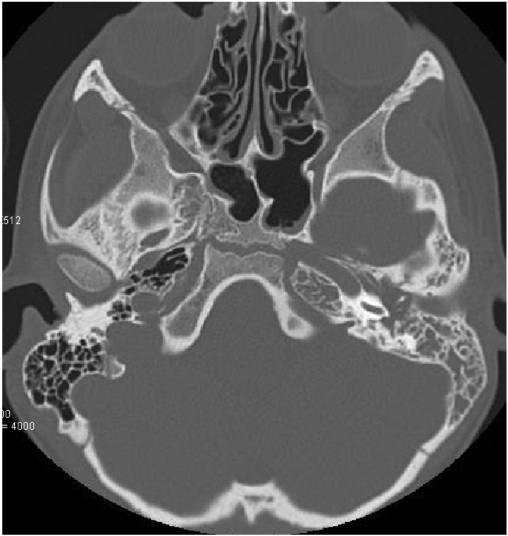

Un bambino di 9 anni viene inviato in urgenza alla nostra attenzione da un Centro periferico per un quadro di cefalea trafittiva occipito-temporale sinistra associata a otalgia sinistra. Il bambino da circa 72 ore lamentava dolore trafittivo all�orecchio sinistro e nelle ultime 24 ore veniva riferita comparsa di febbre accompagnata a vomito alimentare. In anamnesi, nei 20 giorni precedenti l�esordio del quadro emergevano due episodi di otite media acuta sinistra a distanza di circa 10 giorni, trattati con amoxicillina 50 mg/kg/die per os con solo parziale risoluzione del quadro clinico. Il bambino all�ingresso presentava un aspetto visibilmente sofferente, TC 39 �C, membrana timpanica sinistra iperemica e marcatamente estroflessa. Non chiari segni di mastoidite. Per escludere una trombosi dei seni venosi durali eseguiva angio-RM encefalo con riscontro di flogosi mastoidea sinistra (Figura 1).

Figura 1. Angio-RM encefalo con riscontro di flogosi mastoidea sinistra.